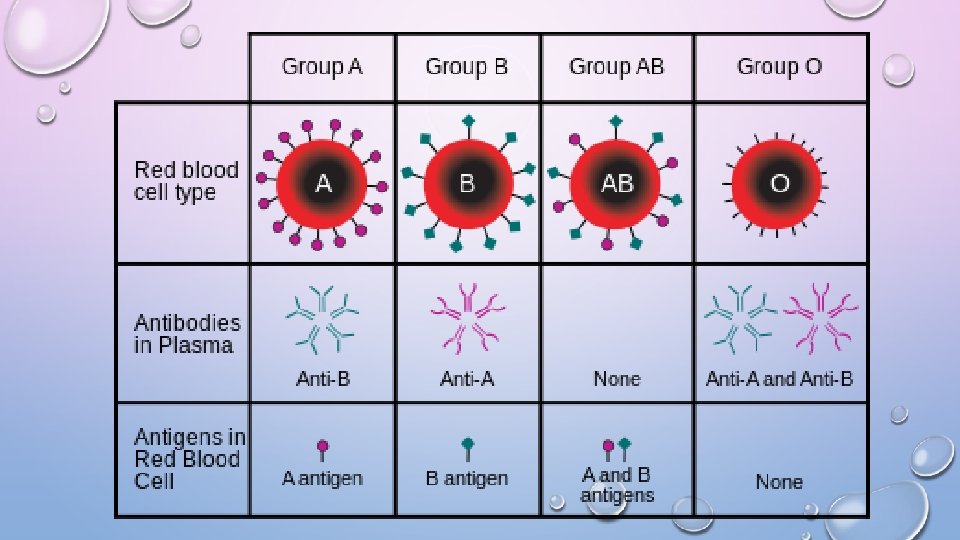

BLOOD PERCENTAGES ON PLANET (APPROX. ) • O+ 38% O- 7% = 46% • A+ 32% A- 6% = 38% • B+ 9% B- 1% = 11% • AB+ 3% AB-. 7% = 4% TRANSFUSIONS • TYPE O UNIVERSAL DONOR • TYPE AB UNIVERSAL RECIPIENT

RH FACTOR • RHESUS MONKEY EITHER YOU HAVE THE PROTEIN (+) OR NOT (-)